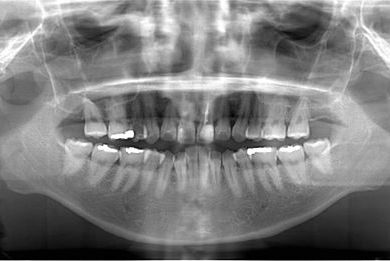

性別/年齢 女性 / 26歳

主訴 虫歯や汚れの治療を希望。

治療方針 セラミック治療にて、審美的回復を行う。

治療内容 メタルボンドセラミッククラウン1本(メタルボンド用土台1本)

治療前